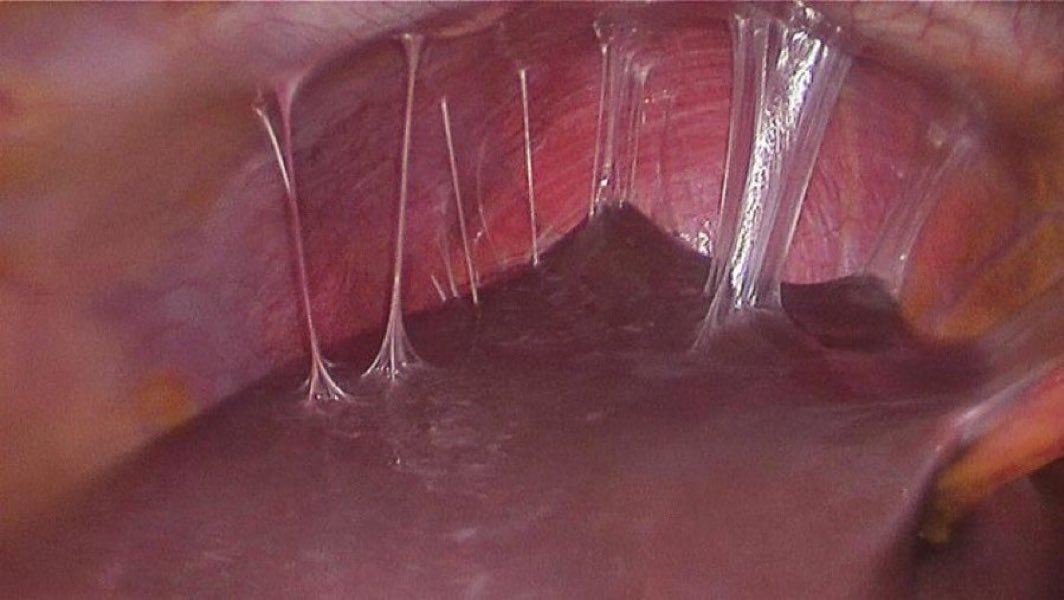

Crohn’s disease on ultrasound: hypoechoic wall thickening (>3 mm) of the terminal ileum with increased Doppler flow – the “comb sign.” Key for diagnosis, activity assessment, and follow-up. #bowelultrasound #Crohns #Ultrasound #IBD #POCUS